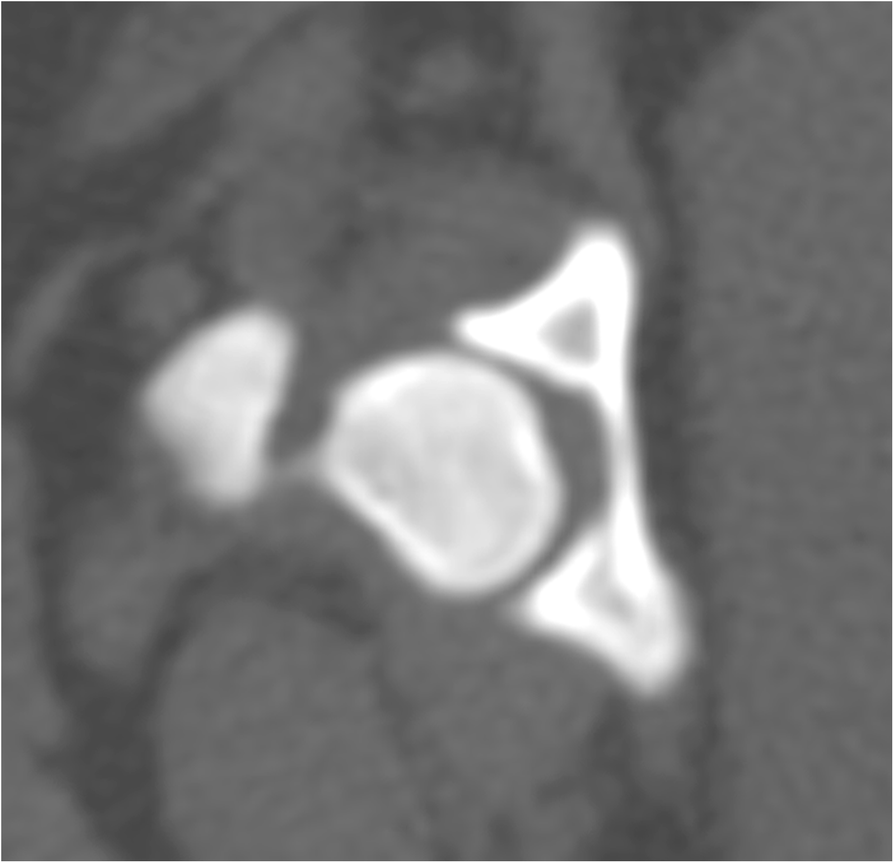

CT scan. Axial (a), sagittal (b), and coronal (c) CT scan images reveal What Is Vacuum Joint Phenomenon Intervertebral vp is usually associated with. It is a very common occurrence, particularly in external rotation. ‘vacuum phenomenon’ or ‘pneumoarthrosis’ term is used when there is air within a joint space. ‘vacuum phenomenon’ or ‘pneumoarthrosis’ term is used when there is air within a joint space. The vacuum phenomenon (vp) refers to collection of gas within the joint space. The. What Is Vacuum Joint Phenomenon.

Spontaneous vacuum phenomenon in the lateral compartment of the knee What Is Vacuum Joint Phenomenon It has been described commonly in the spine and. ‘vacuum phenomenon’ or ‘pneumoarthrosis’ term is used when there is air within a joint space. The vacuum phenomenon (vp) is an anatomical entity that has the potential to cause confusion in the diagnosis and evaluation of joint pathologies. It is a very common occurrence, particularly in external rotation. ‘vacuum phenomenon’ or. What Is Vacuum Joint Phenomenon.